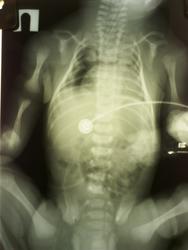

Свежий случай, 3 часа назад. Новорожденный 38-39 недель гестации. Из анамнеза известно, что антенатально виявили аплазию легких и порок серца. Прошу, коллеги, ваши мнения. Особенно меня интересует интерпритация воздуха в грудной полости, так как мнения по этому вопросу разошлись.

Справа возле сердца, дальше выше горизонтальная полоска. Это ткань гипоплазированная, эмфизема или свободный воздух? Бронхограммы никакой тоже не видно... Дыхание прослушивается только в верхних отделах, паратрахеально скажем так. Остальная большая часть легких немая.

Работаете с CR-ом? Диафрагмировать надо по грудной клетке, изображение будет крупнее. Ну, и них, конечно, прикрывать защитой надо, а то можете огрести за несоблюдение радиационной безопасности. Воздух, конечно есть, но где он? Анамнез - это не только антенатальный период, но и неонатальный тоже. Может его эндотрахеально поддули "мама не горюй"? Написал бы - возможны левосторонний пневмоторакс, интерстициальная эмфизема в верхней доле, пневмомедиастинум.

Высказываю свои предположения очень осторожно. Нельзя ли считать пневматизированные отделы правого легкого участками сегментарной эмфиземы? Учитывая,что у ребенка порок сердца,может быть тень, расположенная паракардиально справа является увеличенной v.cava? и тогда субстратом левого гемиторакса может быть увеличенное сердце и аплазированное легкое.

Да, обоих легких. Опредилили на УЗИ в сроке 34 недели, не у нас, во Львове в перинатальном центре. В животе хирурги искали любую зацепку (патология сочетаная).

И так, ничего хорошего не дождались. Патанатомия. По предварительной справке - множественные врожденные пороки развития (легкие, почки, мозг; сердце оценили нормальным). Конкретно по грудной полости - гипоплазия обоих легких, кистозное поражение правого легкого и средостения (вот и наш воздух). Насчет других органов распрашивать детали было не уместно. Подожду офицального документа. К рентгенологу пока претензий нету.

Ренгенолог написал гипоплазию легких, врожденный порок сердца; не исключено правосторонний пневмоторакс, пневмомедиастинум. Насчет воздушных кист средостения сам не знаю, надо покапаться в литературе. Наверное какие-то кистозные мальформации могут быть. Но мое мнение, что свободный воздух всетаки был. Как его доказать на секции? Только вскрыли, он вышел и все.